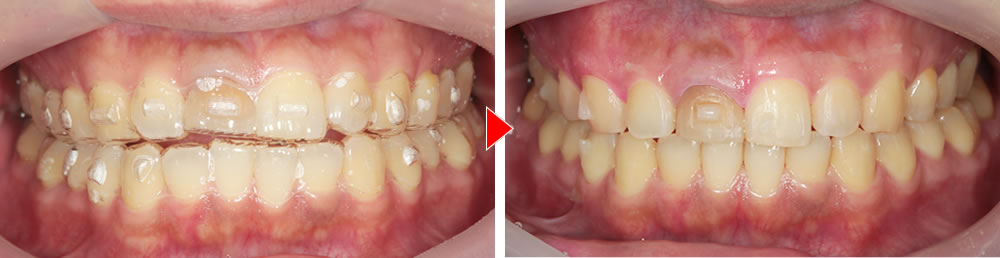

マウスピース矯正装置(インビザライン)による歯並びの改善

まずは「歯並び」を整えるところから始めました。いきなりインプラントを入れるのではなく、最初に行ったのはマウスピース矯正装置(インビザライン)による歯並びの改善です。

約半年間、マウスピース矯正装置(インビザライン)で全体のバランスを丁寧に整え、「前歯を美しく入れるための土台作り」を行いました。